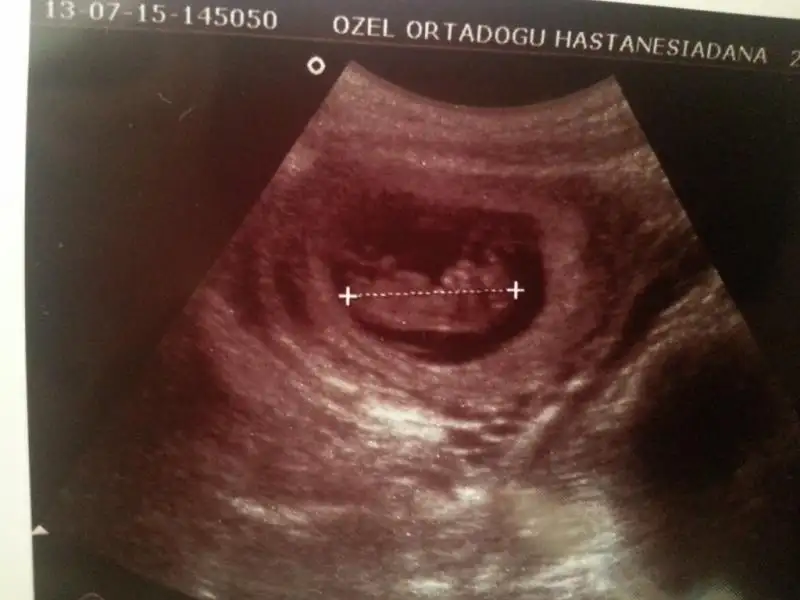

ana senin bebek benimkine göre ters duruyor kafası diğer tarafta maşallah büyümüş ne güzel.